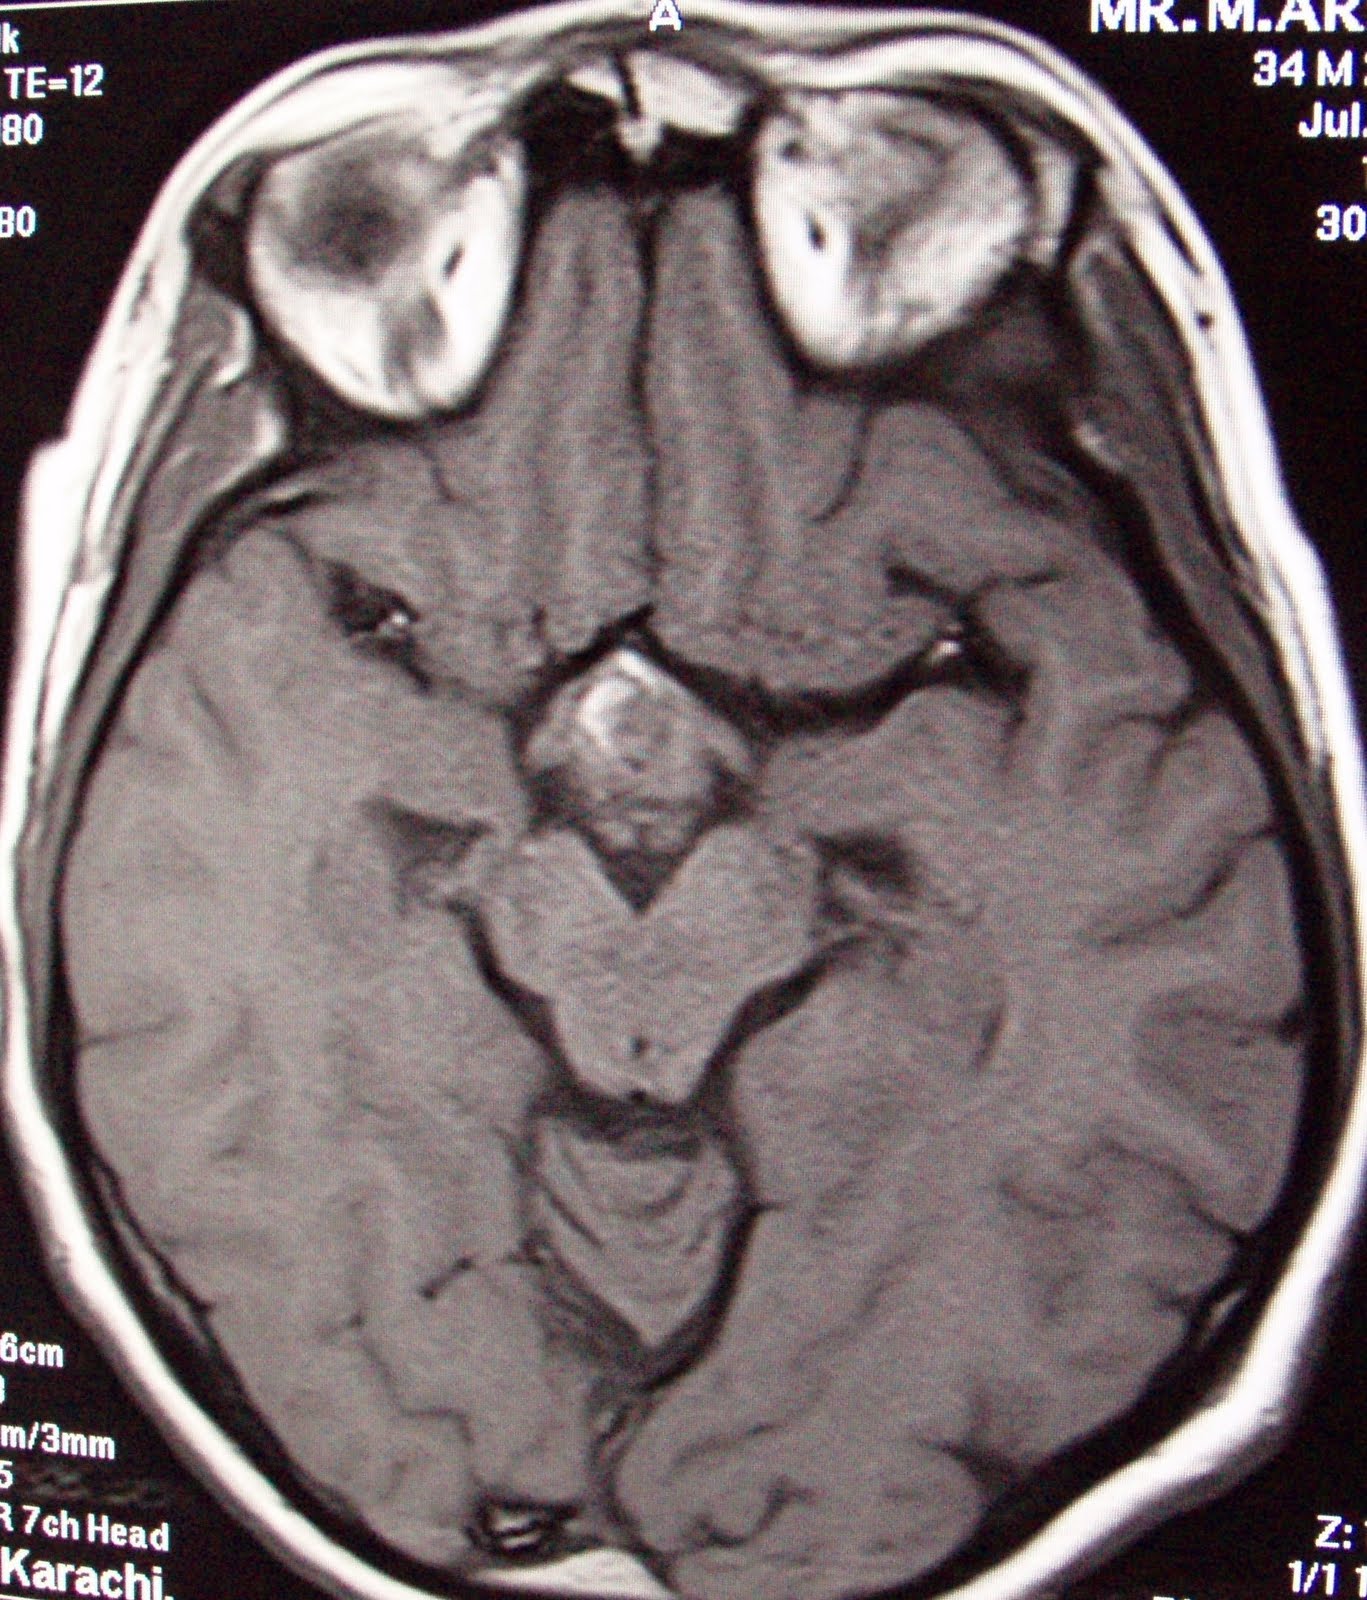

Craniopharyngioma, complete resolution at one year follow up.

This 32 years old male is a diagnosed case of Craniopharyngioma with the diminished vision more on left side, headache and  a single episode of generalized fit since 2 and half years. Under went right frontal craniotomy on 2nd July 2007. MRI scan and CT scans showed residual/recurrent Craniopharyngioma. Patient was treated with 12 GY at 50% isodose line,  for the target volume 7.1 cc, multiple isocenters with 4 and 8mm collimators were used in APS mode.

F.up images after one year showing complete resolution of

craniopharyngioma, clinically patient has normal vision and has no defecits.